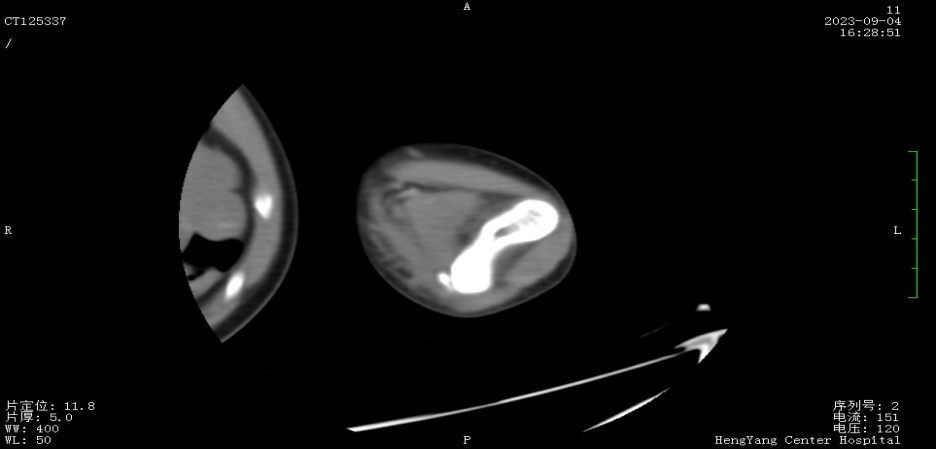

接診后,醫(yī)師發(fā)現(xiàn)小莫同學(xué)的左肘關(guān)節(jié)自然狀態(tài)下僅能伸展至約115°,并伴有習(xí)慣性屈肘。經(jīng)與骨科醫(yī)生溝通并閱片后,考慮骨化肌炎,針對這種情況,一般采取手法松解關(guān)節(jié)和關(guān)節(jié)功能鍛煉相結(jié)合的治療方案。但此方案常用于成人患者的關(guān)節(jié)粘連傳統(tǒng)松解術(shù)和關(guān)節(jié)松動訓(xùn)練,對于兒童來說刺激強度太大,且因兒童骨骼及關(guān)節(jié)較成人脆弱,無法保證治療的連續(xù)性及安全性,若一味采取輕柔手法,不僅治療時間長、見效慢,還可能加重后續(xù)治療難度。

首次治療結(jié)束后,小莫同學(xué)的左肘關(guān)節(jié)即可伸展至145°。9月19日,小莫同學(xué)已結(jié)束第一階段共14次治療,他的左肘關(guān)節(jié)就可以自然伸展至170°,可滿足上肢基本功能需求。